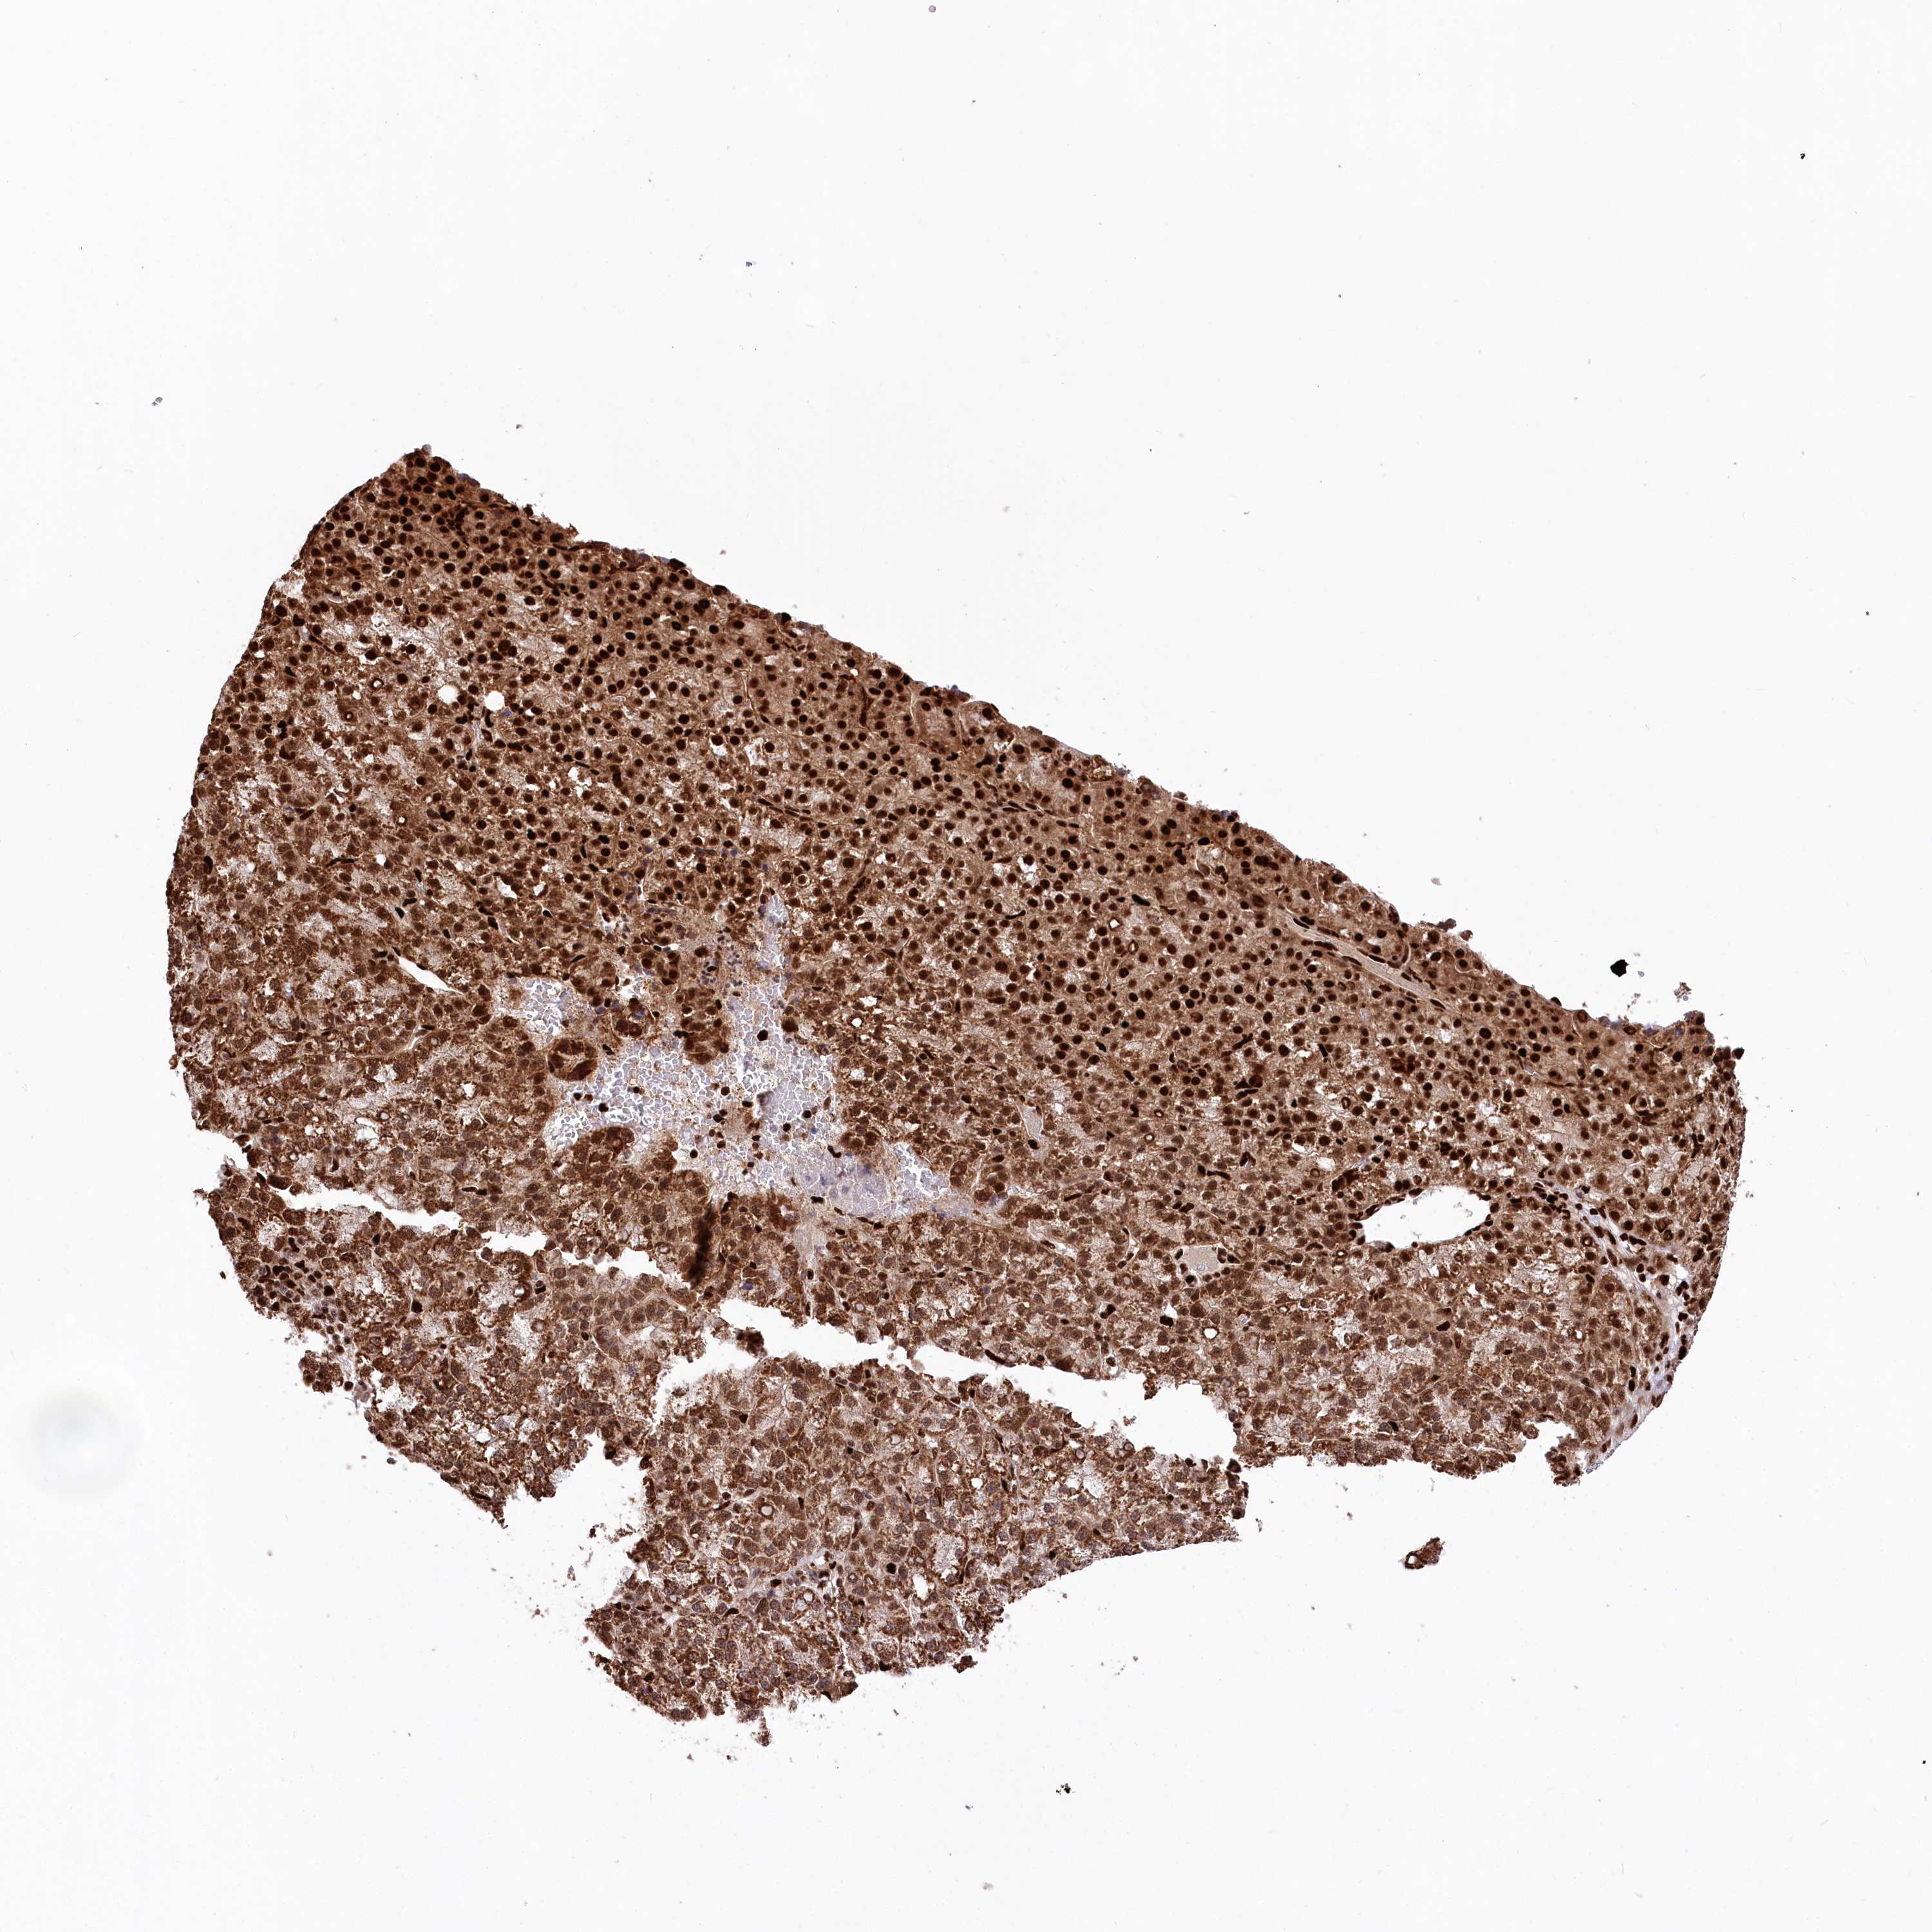

LIVER CANCER - Protein expressioni

A mouse-over function shows sample information and annotation data. Click on an image to view it in a full screen mode. Samples can be filtered based on level of antibody staining by selecting one or several of the following categories: high, medium, low and not detected. The assay and annotation is described here.

Note that samples used for immunohistochemistry by the Human Protein Atlas do not correspond to samples in the TCGA dataset.

Antibody stainingi

Antibody staining in the annotated cell types in the current human tissue is reported as not detected, low, medium, or high, based on conventional immunohistochemistry profiling in selected tissues. This score is based on the combination of the staining intensity and fraction of stained cells.

Each image is clickable and will lead to virtual microscopy that enables deeper exploration of all samples and also displays staining intensity scores, fraction scores and subcellular localization as well as patient and tissue information for each sample.

Antibody HPA034987

Staining

High

Medium

Low

Not detected

Intensity

Strong

Moderate

Weak

Negative

Quantity

>75%

75%-25%

<25%

None

Location

Nuclear

Cytoplasmic/membranous

Cytoplasmic/membranous,nuclear

Cholangiocarcinoma

Carcinoma, Hepatocellular, NOS